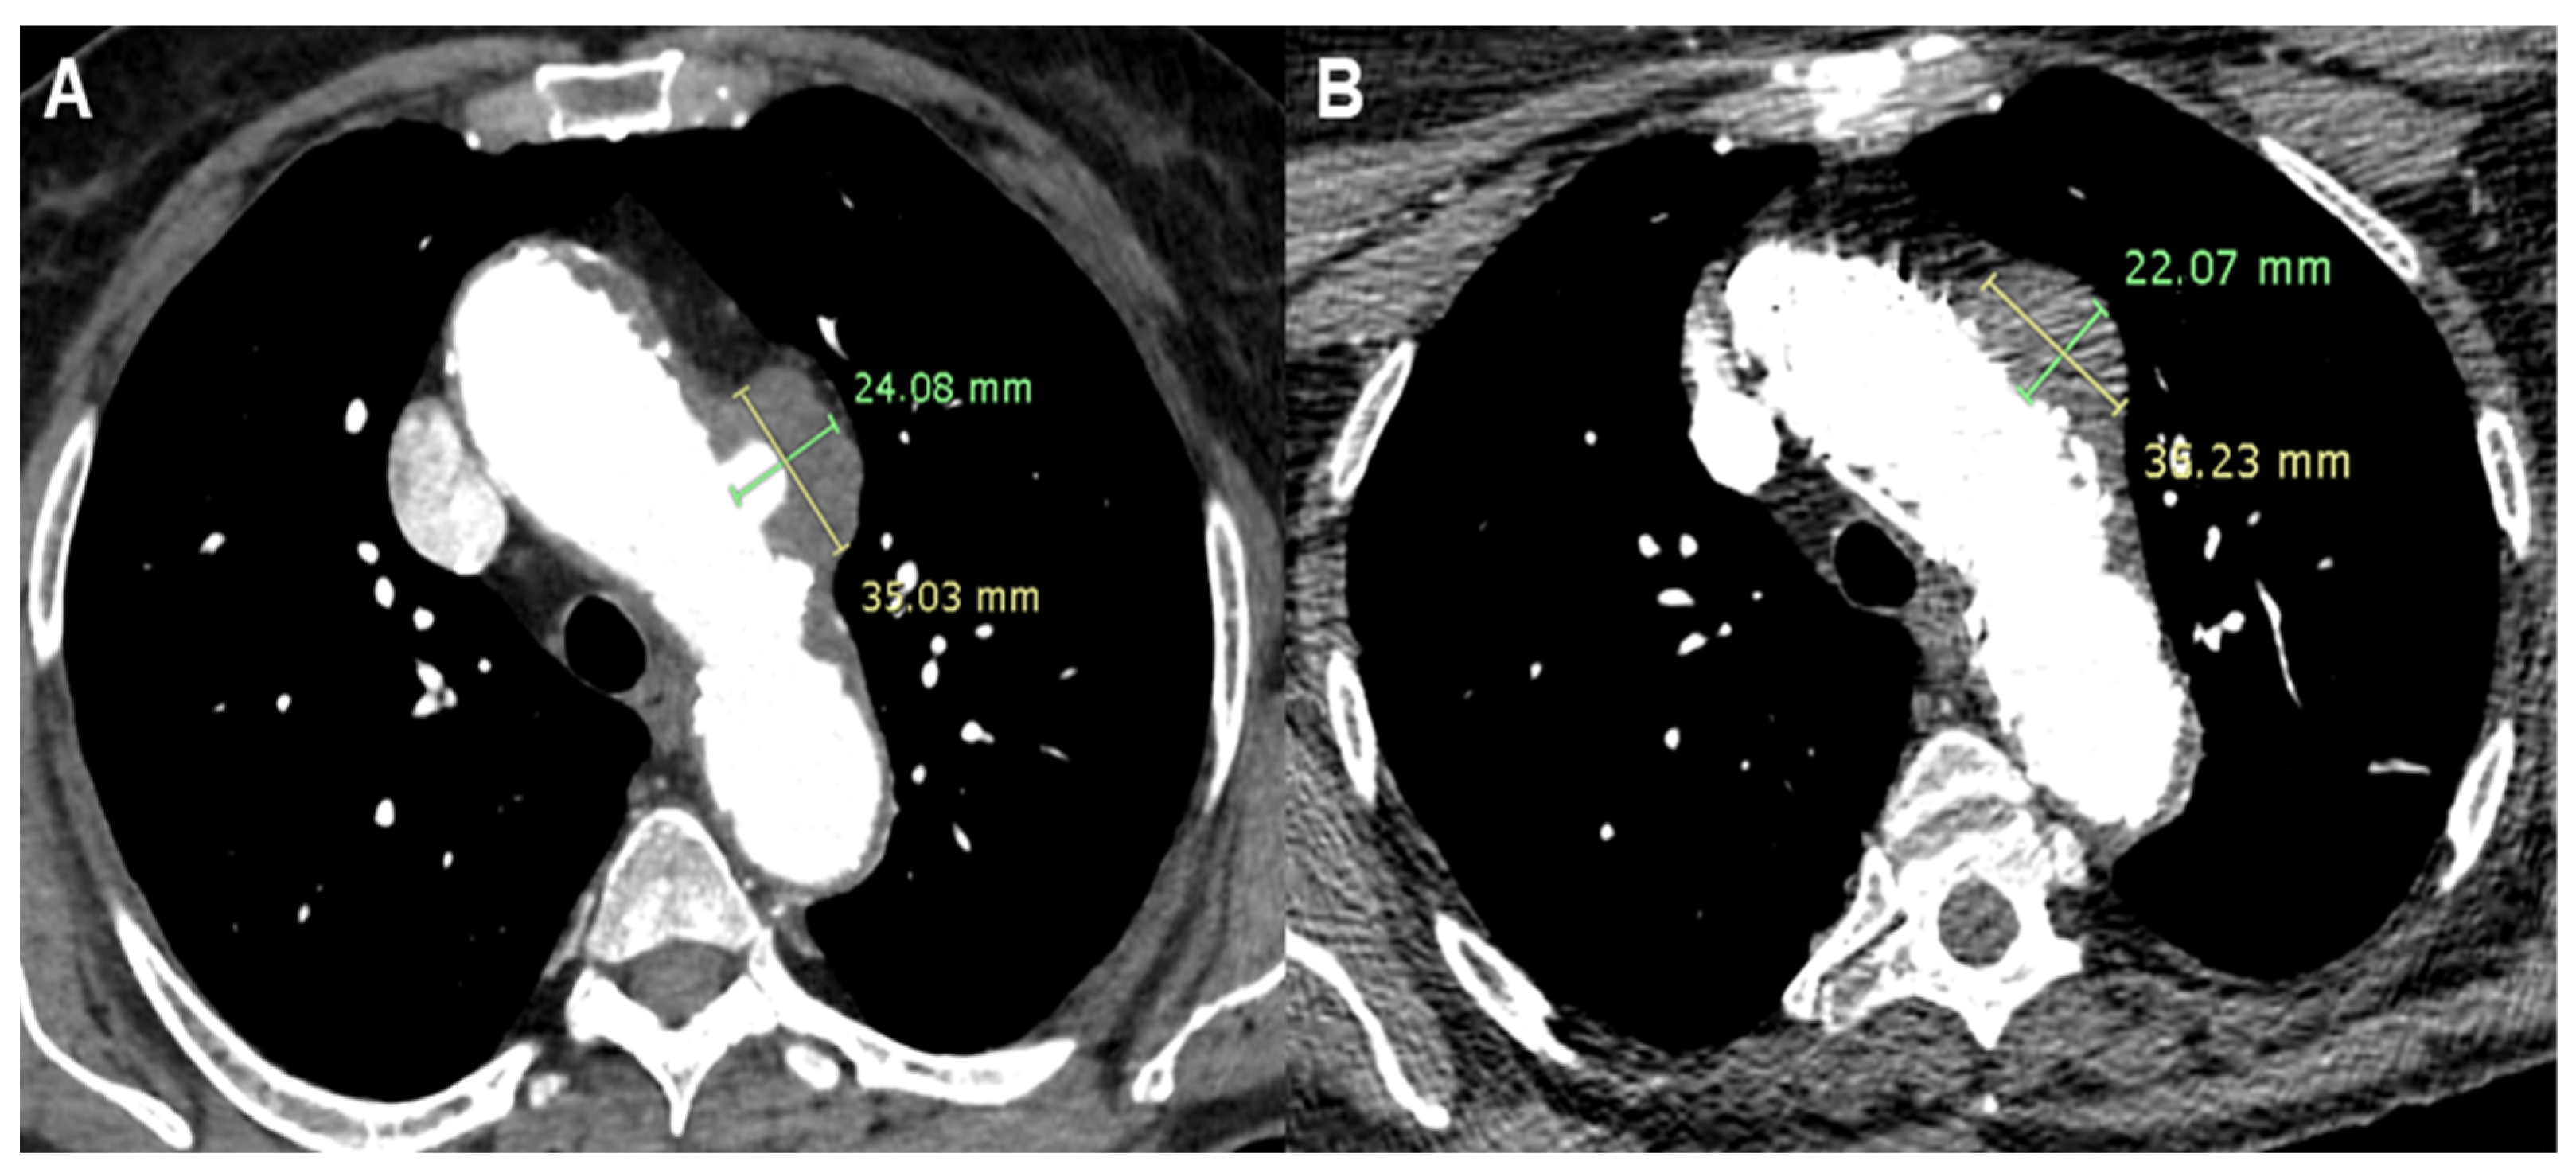

2.1. Patient 1

2.2. Patient 2